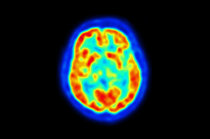

A cintilografia1 pulmonar é um exame da medicina nuclear realizado para avaliar a ventilação2 e a circulação3 sanguínea nas áreas pulmonares. Ela é um método de diagnóstico4 por imagem muito usado para detectar e acompanhar algumas doenças pulmonares e a evolução delas.

A cintilografia1 pulmonar permite avaliar a funcionalidade dos pulmões13. O exame também possibilita analisar as condições dos alvéolos17, além de realizar o diagnóstico4 e acompanhamento de casos de tromboembolismo18 pulmonar (TEP) agudo19 e casos de hipertensão20 pulmonar por TEP crônico21.

A indicação principal se verifica quando há suspeita de tromboembolismo18 pulmonar, caracterizado pela obstrução da artéria pulmonar22 ou de um de seus ramos. Por muitos anos, a cintilografia1 representou o principal método de imagem utilizado na avaliação de pacientes com essa suspeita clínica. Com o advento da tomografia computadorizada23, a cintilografia1 pulmonar deixou de ser o procedimento de escolha no diagnóstico4 de embolia24 pulmonar. Contudo, a cintilografia1 pulmonar por inalação ou por perfusão continua sendo frequentemente usada para detectar problemas de ventilação2 e/ou circulação3 anormal nos vasos sanguíneos25 dos pulmões13, sobretudo quando não se dispõe da tomografia computadorizada23.